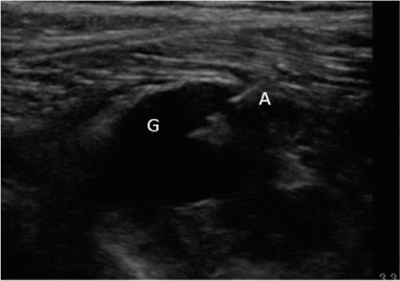

Neuropatía peronea secundaria a ganglión extraneural: revisión de literatura y propuesta de tratamiento. Caso no positivo

Peroneal neuropathy caused by an extraneural ganglion: literary review and treatment proposal. A non-positive case

Este artículo presenta el caso de un paciente de 69 años con una neuropatía compresiva peronea secundaria a un ganglión, inicialmente interpretada como una radiculopatía L5. Este incorrecto enfoque supuso la sobremedicación del paciente, un mal control algésico, la realización de una discectomía L4-L5 innecesaria y una pobre evolución neurológica.

Un enfoque diagnóstico correcto y un abordaje terapéutico precoz habrían supuesto una mayor mejoría clínica e incluso una recuperación neurológica completa del paciente. Por ello, este caso sirve para resaltar: a) el valor de la ecografía en neuropatías periféricas como herramienta diagnóstica y pronóstica y el de la ecografía en gangliones como arma diagnóstico-terapéutica; b) el uso de las pruebas diagnósticas como apoyo a una exploración física exhaustiva, y no como diagnóstico en sí mismas, y c) la importancia de la publicación de casos no positivos para optimizar recursos, evitar repetir errores, reducir el sesgo de publicación y facilitar el inicio de proyectos de investigación.

Figura 1

Figura 2